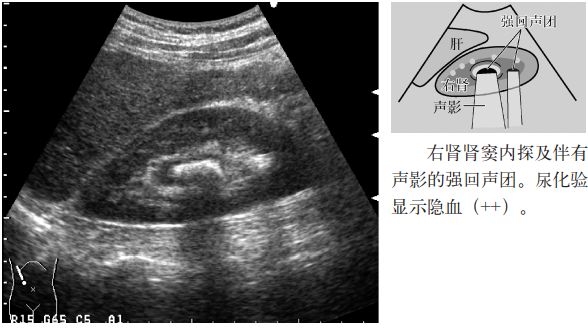

图1 肾结石

注意:小于5mm的肾结石几乎无声影,但是,超声入射角度微妙的变化可以显示点状高回声和声影。因此,平静呼吸时或改变经肋间扫查的位置,有时会出现声影,因此,不仅要在吸气时观察,还应在呼气时或改变经肋间扫查的位置时进行观察。